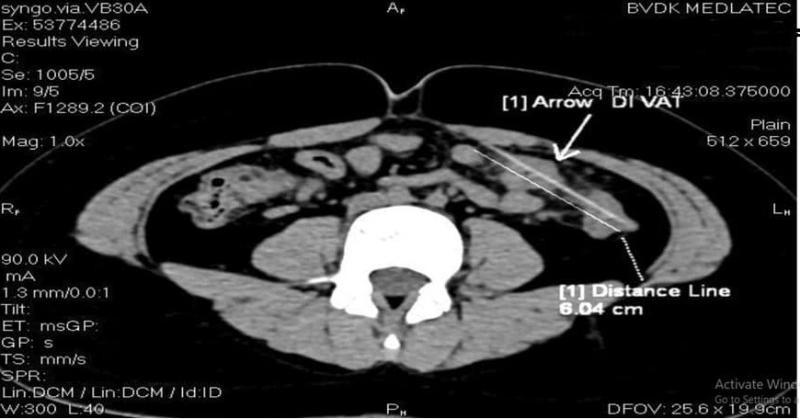

| Hình ảnh dị vật dài 6cm xuyên quai ruột non và đại tràng của bé M khi chụp CT |

Sau 15 phút chụp, kết quả không nằm ngoài dự đoán, hình ảnh chụp cắt lớp vi tính cho thấy dị vật dài 6cm đâm xuyên quai ruột non và đại tràng bên trái.